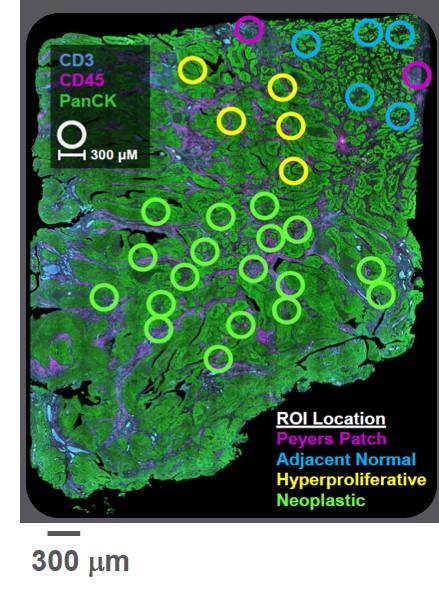

The left image is the GeoMx DSP instrument, the middle image is a sample of regions of interest, or ROIs, in a biological sample that have been selected by a researcher using GeoMx DSP for further analysis, and the right image is a “volcano plot” comparing the differential gene expression across regions within the biological sample.

The primary technologies historically used by researchers and clinicians to analyze gene activity in selected parts of a biological sample include immunohistochemistry, or IHC, which is used to estimate amounts of protein, and in-situ hybridization, or ISH, which is used to estimate amounts of RNA. Both IHC and ISH use fluorescent stains that provide the ability to identify typically four proteins or RNA at a time based on assigned colors. The colors aid researchers in identifying where certain proteins or RNA may reside in a sample and provide a visual approximation of amounts. These techniques are generally limited however in their ability to only look at four proteins or RNA at a time and offer no ability to precisely quantify the amounts present in any given region or cell type. These limitations may lead to incomplete scientific conclusions as to the most relevant biological pathways in any given sample.

GeoMx DSP is designed to allow researchers to quantify a much larger number of RNA or proteins spatially within multiple regions of interest across the landscape of a heterogeneous section of a biological sample. Our GeoMx DSP instrument images slide-mounted or freshly cut sample sections, allowing users to select regions of interest for subsequent quantification and analysis, or molecular profiling. The post-selection profiling or “read out,” can be performed using either our nCounter Analysis System, or an Illumina NGS system.

We believe GeoMx DSP offers a number of advantages as compared to traditional spatial technologies, including the ability to profile both RNA and protein, the ability to multiplex large numbers of different RNA or proteins simultaneously in each selected region, flexibility on the selection of regions to analyze, and the ability to process 10 or more biological samples per day.

When GeoMx DSP was first made commercially available, researchers were only able to read out information on up to 96 biological targets from each of their GeoMx-selected regions of interest using nCounter. In August 2020, we added software capabilities and consumables which enabled GeoMx region of interest data to be read out using Illumina NGS systems, which significantly expanded the number of biological targets researchers can choose to analyze in selected regions. Linking GeoMx DSP with NGS also significantly expands our total potential market opportunity. As of December 31, 2021, there were approximately 20,000 Illumina NGS systems installed globally.